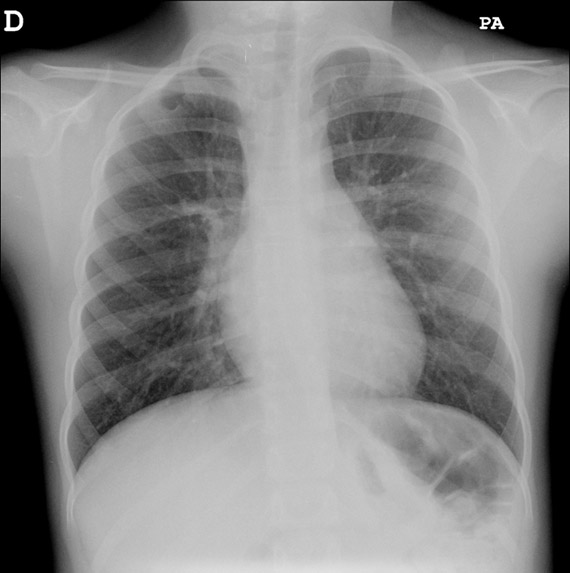

¿Encuentra algún hallazgo en esta radiografía?

Es recomendable ser metódicos en la evaluación de la radiografía de tórax. Debido a que la radiografía suele realizarse para examinar el parénquima pulmonar, sugerimos comenzar por revisar el resto de estructuras, como la pared torácica, la vía aérea y los hilios pulmonares, sin dejar de observar el cuello y el hemiabdomen superior incluidos en la placa2,3: